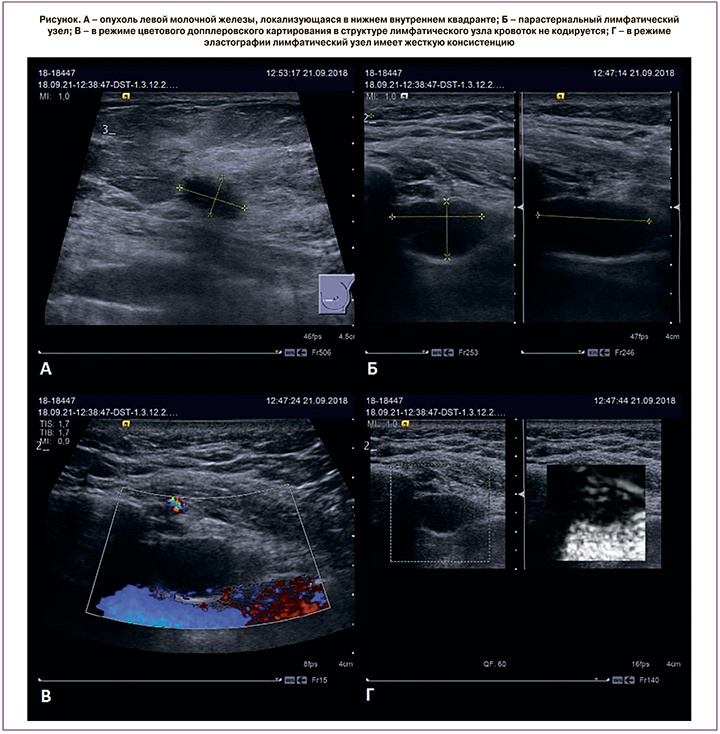

Ультразвуковое исследование (УЗИ)

Использует звуковые волны для создания изображения в реальном времени.

➕Сильные стороны: отлично показывает структуру лимфоузла, может оценить его форму, контур и состояние кровотока. Превосходно подходит для исследования поверхностно расположенных лимфоузлов: подмышечных, шейных, под- и надключичных, паховых. Это лучший инструмент для прицельной биопсии, когда под контролем УЗИ иглой берут клетки или столбики ткани из подозрительного узла для анализа. Метод абсолютно безопасен, лучевая нагрузка нулевая.

➖Ограничения: точность метода сильно зависит от опыта врача-диагноста. Внутригрудные лимфоузлы недоступны для УЗИ-диагностики, так как ультразвук не проходит через воздух в легких или кости.

Роль в диагностике: первичный, скрининговый и уточняющий метод для доступных зон. Метод выбора для проведения качественной биопсии.

· Рак молочной железы: первым делом — УЗИ подмышечных, подключичных и шейных областей, часто с биопсией подозрительных лимфоузлов. Для оценки глубоких внутригрудных лимфоузлов - КТ грудной клетки. МРТ молочных желез назначается для уточнения размера и характера первичной опухоли.